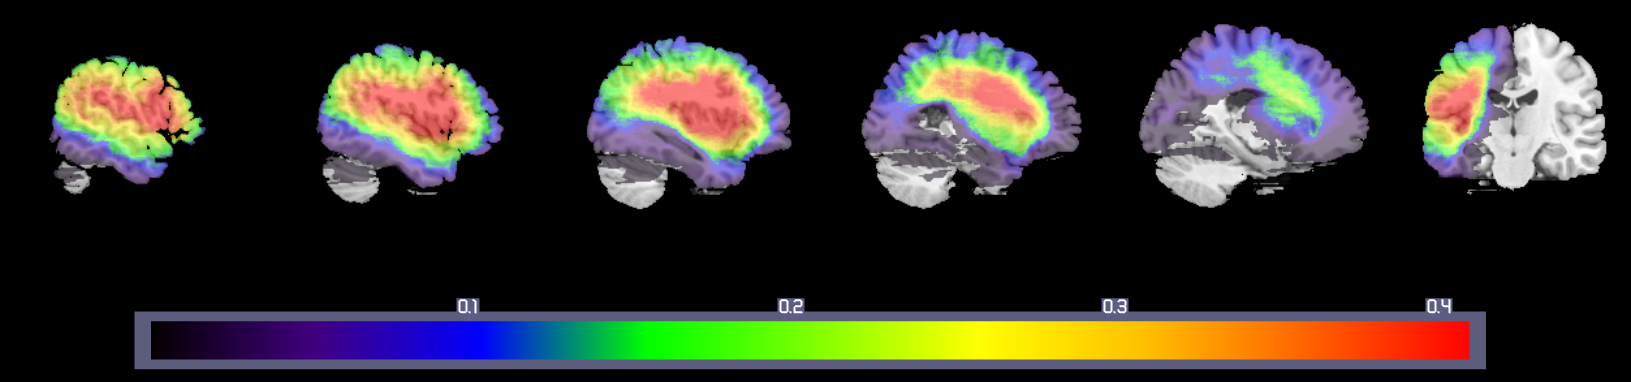

The lesion maps were from 124 participants with aphasia following left hemisphere stroke confirmed by computed tomography (CT) or magnetic resonance imaging (MRI). The structural data were based on 108 research scans (65 MRI and 43 CT) and 16 clinical scans (5 MRI and 11 CT). Lesions imaged with MRI were manually segmented on the structural image by a trained technician and reviewed by an experienced neurologist, then registered first to a custom template constructed from images acquired on the same scanner, and then from this intermediate template to the Montreal Neurological Institute space ‘Colin27’ volume. Lesions imaged with CT were drawn by the experienced neurologist directly onto the Colin27 volume, after rotating (pitch only) the template to approximate the slice plane of the patient's scan. Figure 1 shows the lesion overlap map for these 124 lesion maps, which have been used in VLSM analyses reported elsewhere (Mirman et al., 2015a, ; Mirman et al., 2015b, ) and are part of a larger, ongoing project investigating the anatomical basis of psycholinguistic deficits in post-acute aphasia222That project has been funded by National Institutes of Health grant R01DC000191 to Myrna F. Schwartz and we are grateful to Dr. Schwartz and her team for sharing these data with us and making these analyses possible..

In order to have a deficit score with a known neural correlate, we calculated the percent damage in two brain regions that are widely-studied and frequently damaged in middle cerebral artery stroke aphasia: BA 45 and BA 39 (see Figure 1). An effective statistical correction strategy should approximately identify these areas (i.e., damage in BA 45 is the ``neural correlate" of percent damage in BA 45) and the permuted data will provide additional insight into the method’s ability to reject false positives.